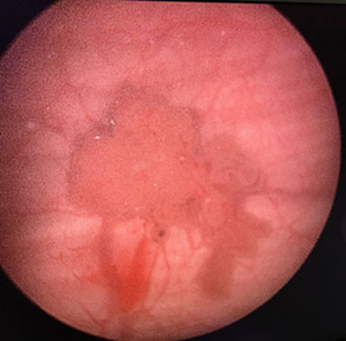

Endoscopic view of Bladder Tumor Before TURBT Surgery

Transurethral Resection of a Bladder Tumour (TURBT) –Cancerous bladder tissue is removed through the urethraSubsequently, chemotherapy or immunotherapy can be directly given inside the bladder through urinary catheter.